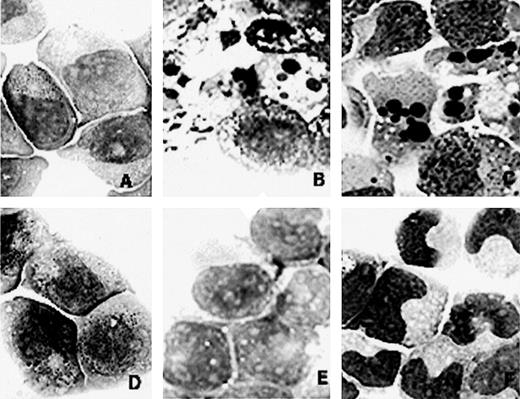

Morphology of NB4 (A, B, and C) and NB4/As (D, E, and F) cell lines on RA or the combination of RA and As2O3 treatment. (A and D) Before treatment. (B and E) After 1 day of treatment with 1 μmol/L As2O3. (C) After 1 day of treatment with 1 μmol/L all-trans RA and 1 μmol/L As2O3. (F) After 4 days of treatment with 1 μmol/L RA and 1 μmol/L As2O3.

Finally, our recent data suggested that constitutive degradation of PML-RARα is not necessarily associated with RA-resistance. We established a new subline of NB4 (NB4/As) that showed resistance to As2O3: continuous growth without apoptosis and differentiation in the medium containing 1 μmol/L As2O3. In immunoblot analysis, a PML-RARα band of this cell line disappeared in the presence with As2O3 and reappeared after the removal of As2O3 (data not shown). As2O3 is known to modify PML as well as to accelerate the degradation of PML-RARα.6-8 Although the molecular mechanism of the As-resistance is under investigation, the addition of RA differentiated NB4/As and increased the nitroblue tetrazolium (NBT) reduction activity even in the coculture with As2O3 (Fig 1).